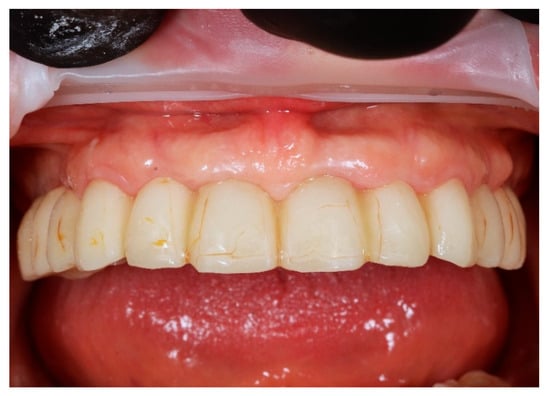

The restoration was torqued in line with the manufacturer’s specifications, and the screw access channels were sealed with composite resin. The definitive clinical situation in the patient’s mouth is shown in Figure 18 and Figure 19.

Figure 18. Extraoral frontal view of the definitive full-arch prosthesis in situ, demonstrating the final aesthetic outcome.